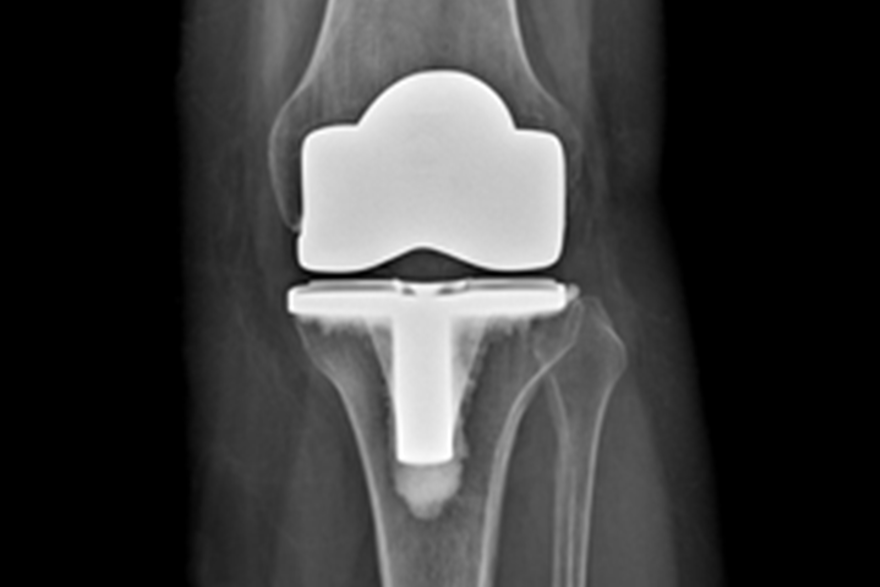

Kneprotesen er ein erstatning for øydelagde leddflater i kneet. Den består av 2 metalldelar som vert festa på lårbeinet og skinnebeinet. Leddflata på lårbeinet består av metall, leddflata på skinnebeinet av høgforedla plast. Metalldelane vert festa med eller utan beinsement. Ei totalprotese dekkjer heile leddflata både på lårbeinet og på skinnebeinet. Det pre- og postoperative forløpet er likt for alle protesetypane.